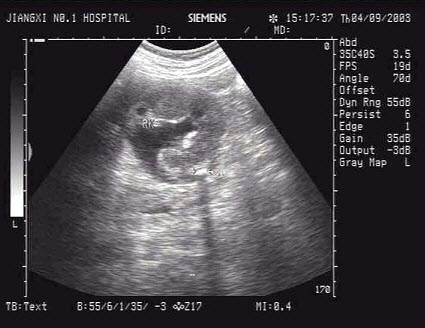

D.玻璃体后脱离

女性,25岁,停经35周。产前超声检查,图像显示的是胎儿的()